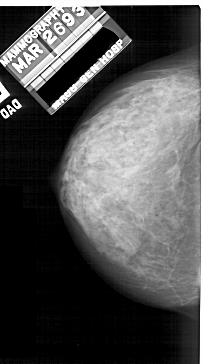

A_1912_1.LEFT_MLO

LEFT_MLO LINES 5491 PIXELS_PER_LINE 2881 BITS_PER_PIXEL 12 RESOLUTION 43.5 NON_OVERLAY